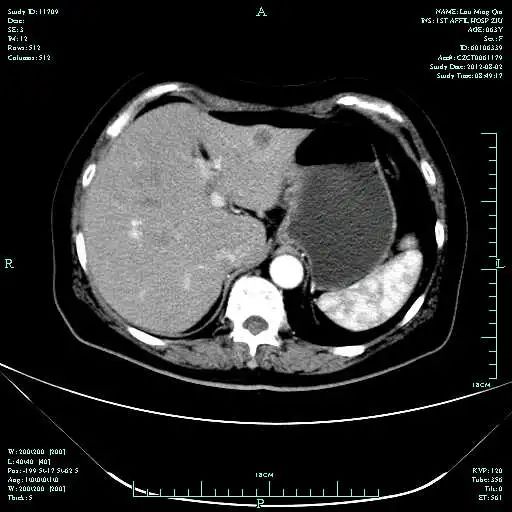

CT-T

CT-H1

MR-H1

影像学检查结果评估:cPD。